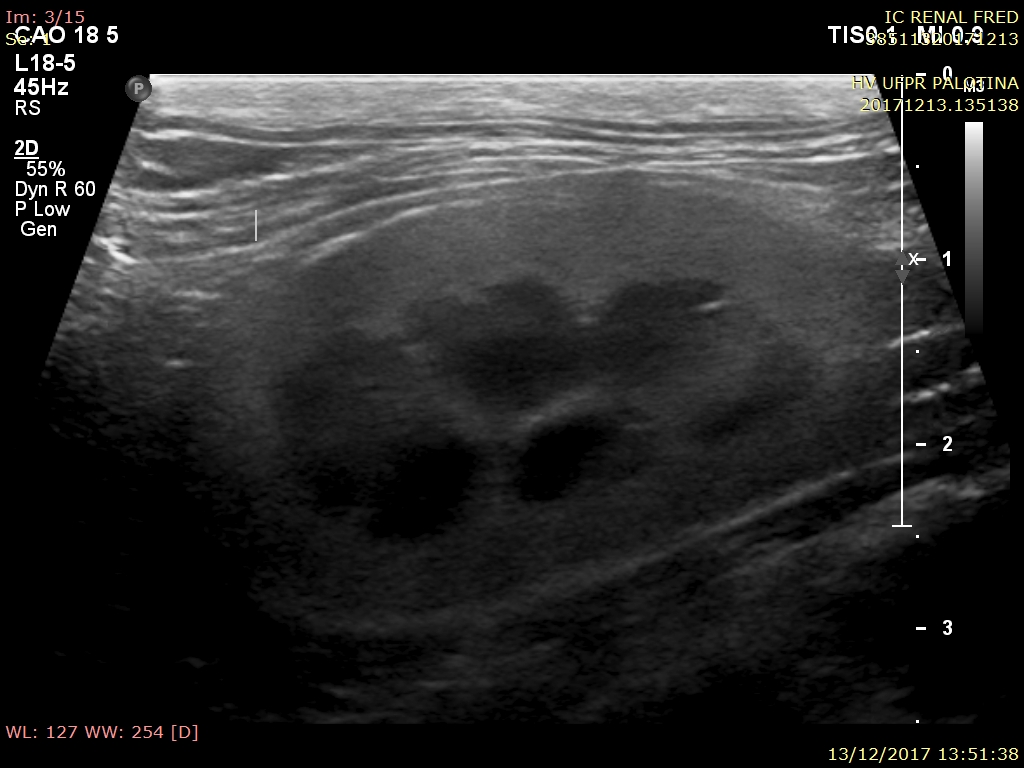

O exame ultrassonográfico é uma ferramenta diagnóstica imprescindível na avaliação da integridade renal, já que fornece informações importantes a respeito da arquitetura e das dimensões renais. Os rins são facilmente visualizados na ultrassonografia, a qual permite avaliar o parênquima do órgão, diagnosticar possíveis afecções, e monitorar o grau de comprometimento tecidual. Os gatos apresentam predisposição ao desenvolvimento de nefropatias, especialmente os mais idosos, por isso o uso do ultrassom demonstra alto grau de importância no diagnóstico precoce. O presente trabalho avaliou 12 gatos provenientes da rotina do Hospital Veterinário da Universidade Federal do Paraná, Setor Palotina, nos quais o tamanho renal demonstrou média e desvio padrão de 3,52 ± 0,45cm para o rim esquerdo e 3,64 ± 0,34cm para rim direito, a ecogenicidade de cortical se mostrou aumentada em sua maioria, sendo um achado normal devido ao acúmulo de gordura tubular. Os parâmetros de topografia, forma, contorno e características de pelve renal se mostraram dentro da faixa de normalidade, sendo as alterações em relação e diferenciação corticomedular, e ecogenicidade de cortical as de maior importância.